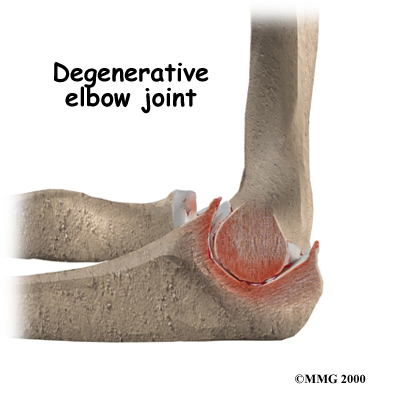

OA is caused by degeneration of the articular cartilage of a joint. Degeneration is wear that happens over time. Doctors use the term degenerative arthritis to describe the wear and tear of a joint over many years. Degenerative arthritis is another term for OA. Some doctors use the term degenerative arthrosis. Arthrosis means that the joint is wearing out.

OA is caused by degeneration of the articular cartilage of a joint. Degeneration is wear that happens over time. Doctors use the term degenerative arthritis to describe the wear and tear of a joint over many years. Degenerative arthritis is another term for OA. Some doctors use the term degenerative arthrosis. Arthrosis means that the joint is wearing out.

An injury doesn't have to directly damage the articular cartilage to start the process of OA. Any injury to the elbow joint can change the way the joint works which then starts the cycle of wear and tear on the joint. For example, after an elbow fracture the bone fragments may not line up exactly. If this is the case they then heal in a slightly different position from prior to the injury, which may only mildly modify how the joint works, but is enough to change the wear and tear on the cartilage.

A dislocation can also cause lasting damage to the elbow joint. After the ligaments have been injured in a dislocation, the elbow joint may move differently. This change in movement alters the forces on the articular cartilage. Similar to how a machine works, if one mechanism is out of balance, there can be more friction between the moving parts and it wears out faster.

Over many years, this imbalance in joint mechanics can damage the articular cartilage. Since articular cartilage cannot repair itself very well, the damage adds up. Finally, the joint can no longer compensate for the damage, and the elbow begins to hurt.

OA of the elbow is a similar process to that which occurs in the hip or knee, however, more often in the elbow, the articular cartilage itself isn’t damaged with an initial injury, whereas in the hip or knee it often is. In the elbow the biggest changes occurring after an injury are hypertrophic osteophyte (bone spur) formation and capsular contracture.

Capsular contracture refers to the process by which the capsule dries out and tightens up. The capsule has two layers: a fibrous covering that surrounds the joint and an inner lining. The inner layer is called the synovium. The synovial layer holds the lubricating fluid inside the joint. If this fluid dries up, or the joint capsule contracts, the mechanics of the elbow joint change, and this in turn applies more pressure to the articular cartilage and wears it out quicker.